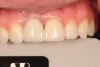

The patient healed well, and in 4 months the implant was uncovered with a simple punch uncovering technique. One month later, the restorative dentist placed a custom provisional restoration to begin molding the soft tissue. There was a small black space between the central incisors, partly due to the triangular shape of tooth No. 9 and slight papilla shrinkage on the mesial of No. 9. A small gingival composite was placed on the mesial of No. 9 to mimic the contour of the provisional crown. The tissue was molded for 4 months, and the final restoration was placed (Figure 23).

Fig 23. Final restoration at 4 months. A provisional restoration was used to mold the tissue prior to placement of the final restoration.

Figure 23